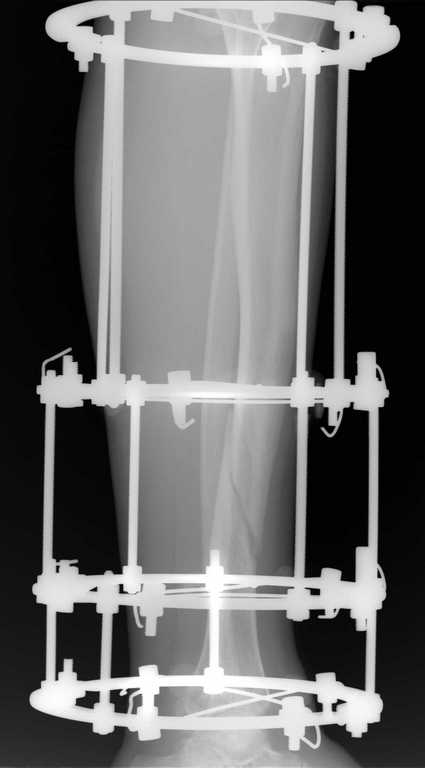

Уважаемые коллеги, доброго времени суток. Пациент 40 лет, получил травму в марте 2010 г, на следующий день прооперирован ЧКДО по Илизарову.

последние снимки от 15.07.10. Пациент передвигается с полной нагрузкой на оперированную конечность, болей нет. Вопросы: 1. снимать аппарат? 2. если снять и появится подвижность, что делать? 3. возможно ли в такой "изогнутый" канал большеберцовой кости установить штифт, если да, то какие могут быть сюрпризы? Заранее спасибо.

На снимке спицы расположены поперечно без признаков компрессии. Аппарат в нейтральном режиме, а нагрузка идет за счет аппарата. На месте перелома образовалась щель, и здесь отсутствуют условия для сращения.

После 6 месяцев трудно поверить, что дополнительными спицами и нагрузкой можно исправить положение. Поэтому на данном этапе можно было бы ограничится ревизией аппарата. Если все спицы установлены в норме, тогда, не теряя времени, надо сделать остеотомию на малоберцовой.

Необходимо добиться компрессии во время операции, и сделанный снимок на столе подскажет, удалось ли добиться успеха.